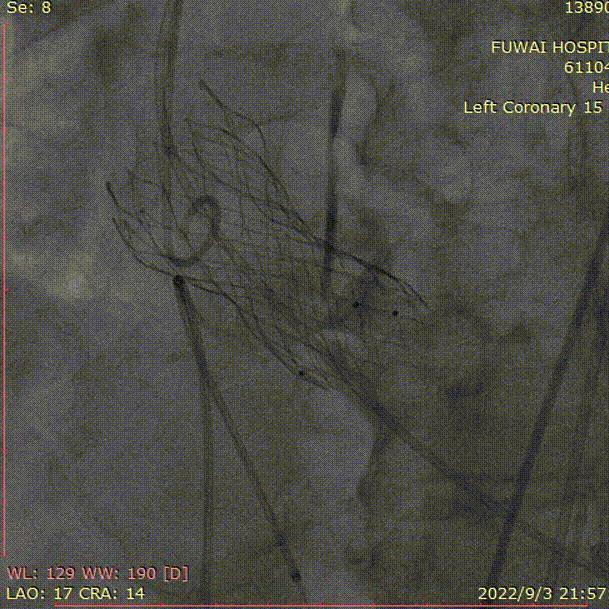

1、冠脉造影和抉择急诊PCI和急诊TAVR

左冠造影